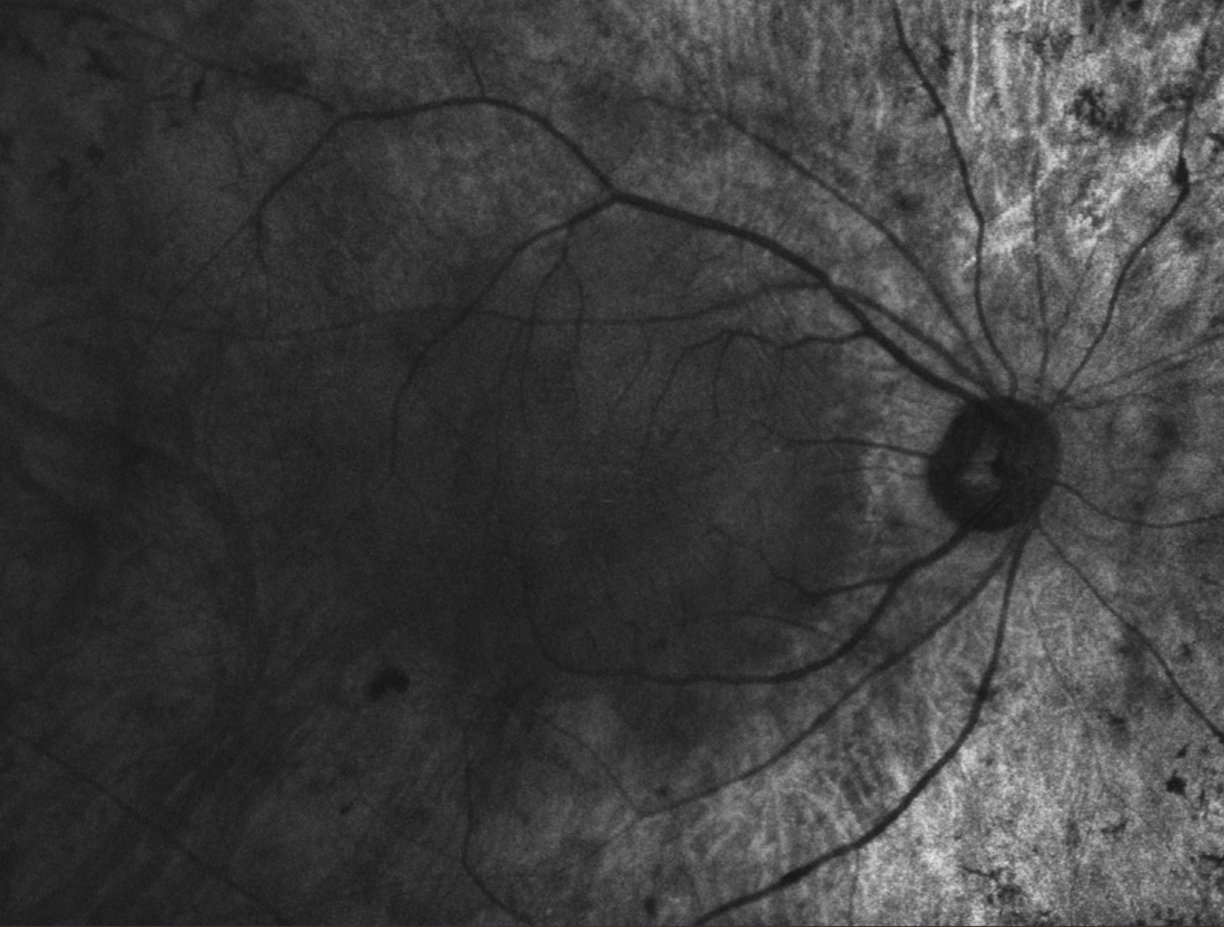

Пігментний ретиніт (пацієнт з артифакією) зображення отримане за допомогою ретинальної камери Canon CR-2 plus AF в режимі FAF

Пігментний ретиніт (пацієнт з артифакією) СЛО-зображення отримане за допомогою оптичного-когерентного томографа Canon Xephilio OCT A1